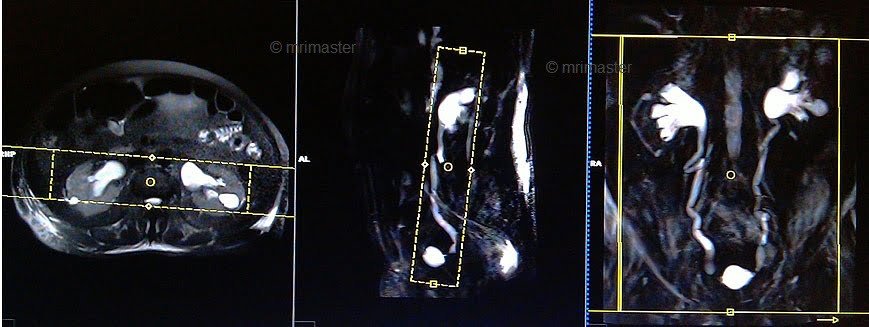

T2 HASTE thick 60mm breath hold coronal oblique(single slice)

Plan the coronal slice on the axial plane; angle the positioning block parallel to the right and left kidneys. Check the positioning block in the other two planes. An appropriate angle must be given in the sagittal plane (parallel to the ureter). Slice thickness must be sufficient to cover the entire ureters. Phase oversampling must be used to avoid wrap-around artifacts. FOV must be big enough to cover the kidneys and bladder. Instruct the patient to hold their breath during image acquisition.

Parameters

TR 3000-4000 | TE 500 | FLIP 150 | NEX 1 | SLICE 60mm | MATRIX 384X320 | FOV 400-450 | PHASE R>L | OVERSAMPLE 50% | IPAT ON |

T2 haste thick 60mm breath hold sagittal oblique(single slice) RT

Plan the sagittal slice on the coronal plane; angle the positioning block parallel to the right ureter. Check the positioning block in the other two planes. An appropriate angle must be given in the axial plane (perpendicular to the right kidney calyx). Slice thickness must be sufficient to cover the whole ureter. Phase oversampling must be used to avoid wrap-around artifacts. The field of view (FOV) must be big enough to cover the kidneys and bladder. Instruct the patient to hold their breath during image acquisition.

TR 3000-4000 | TE 500 | FLIP 150 | NEX 1 | SLICE 60mm | MATRIX 384X320 | FOV 400-450 | PHASE A>P | OVERSAMPLE 50% | IPAT ON |

T2 haste thick 60mm breath hold sagittal oblique(single slice) LT

Plan the sagittal slice on the coronal plane; angle the positioning block parallel to the left ureter. Check the positioning block in the other two planes. An appropriate angle must be given in the axial plane (perpendicular to the left kidney calyx). Slice thickness must be sufficient to cover the whole ureter. Phase oversampling must be used to avoid wrap-around artifacts. The field of view (FOV) must be big enough to cover the kidneys and bladder. Instruct the patient to hold their breath during image acquisition.